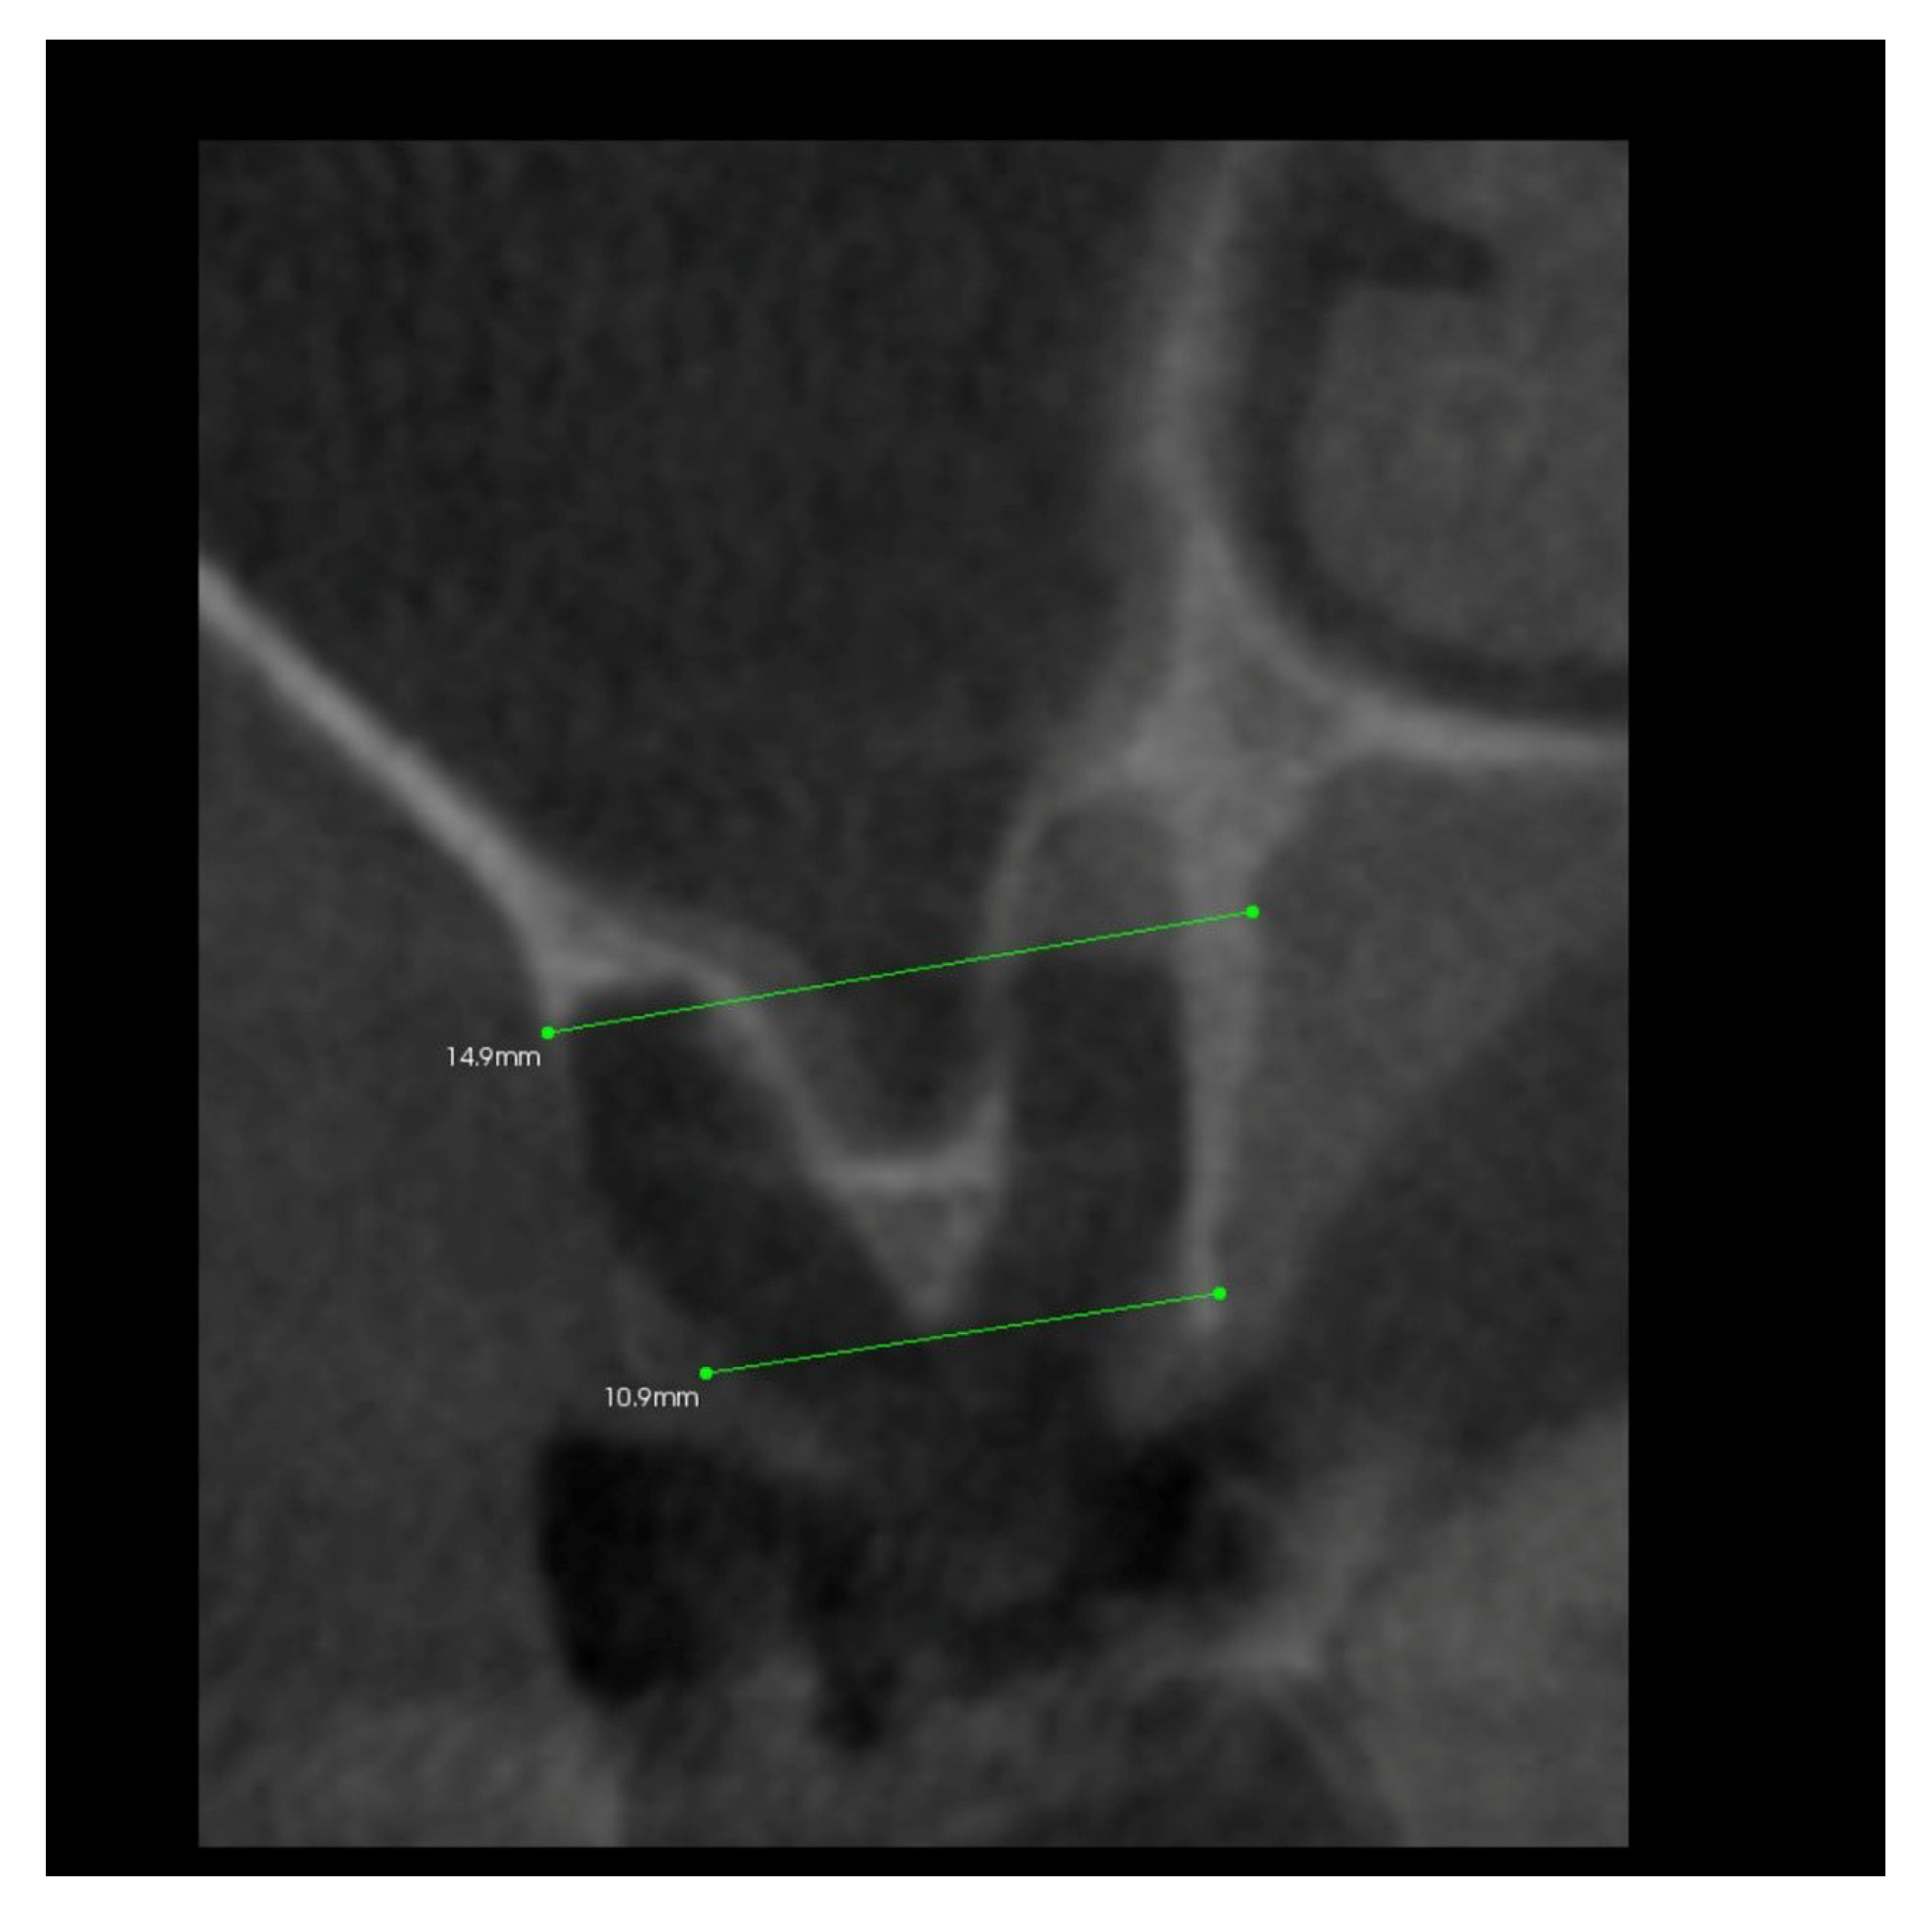

Simultaneously, after 10 days from the surgery, the patient was subjected to CBCT (cone beam computed tomography) examination, limited to the area of the post-extraction alveoli using the Kodak 9000 apparatus (Figure 5), and the alveolus width and height were measured.

Figure 5.

Transverse imaging of maxillary alveolus obtained from CBCT. The alveolus width measurement 10 days post-extraction.

In addition, 6 months after the surgery, another performance of volumetric CBCT limited to the area of the post-extraction alveoli using the Kodak 9000 apparatus was recommended. During these examinations, the alveolar process in the extraction site and grayscale values in the selected measurement points were measured (Figure 6, Figure 7, Figure 8 and Figure 9).

Figure 6.

Transverse imaging of maxillary alveolus in CBCT. Alveolar width measurement 6 months post-extraction.